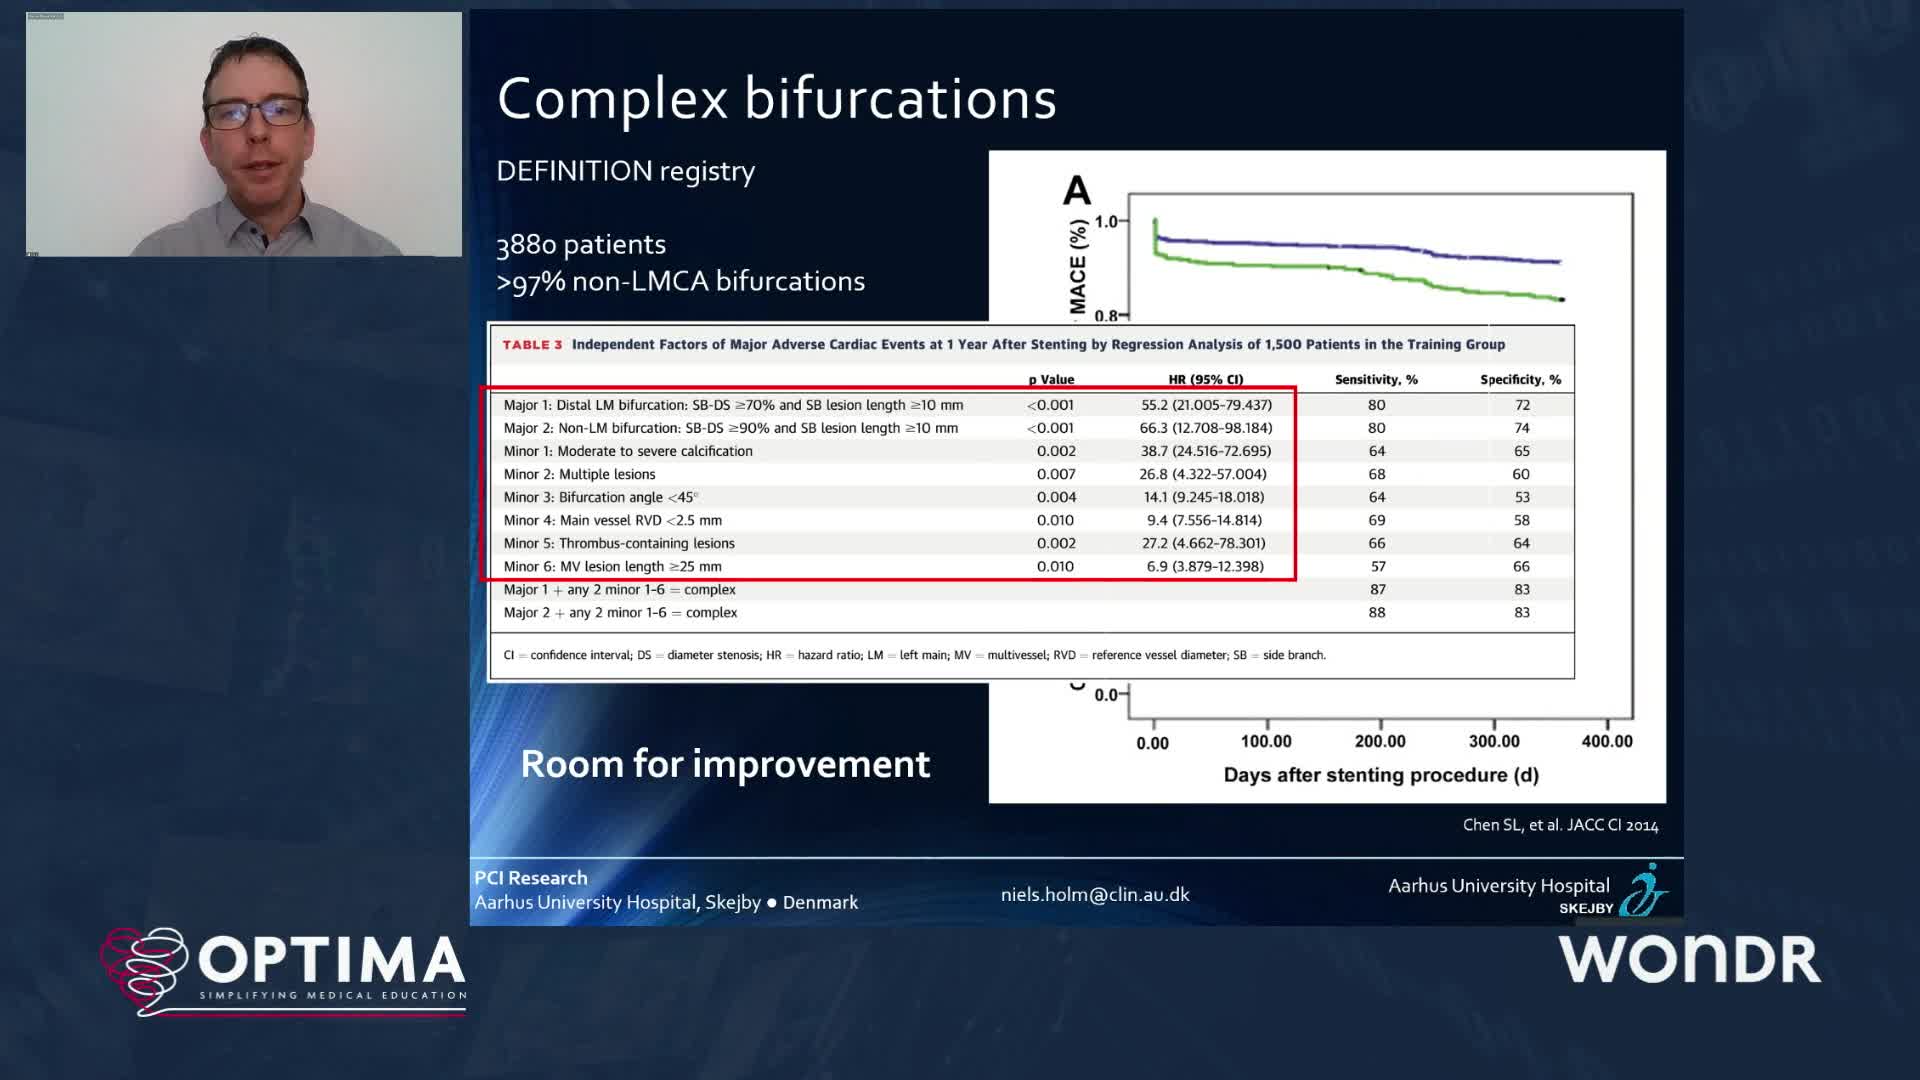

The integrated use of physiology and imaging is transforming the treatment of complex bifurcation disease. We explore...